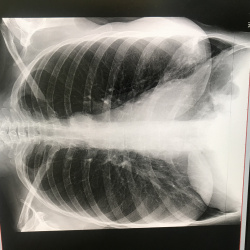

Здравствуйте, подскажите, женщина 45лет, на узи образовани  пониженной эхогенности с кистозной дегенерацией, направил онколог, здесь количество лимфоузлов около трахей нормально?